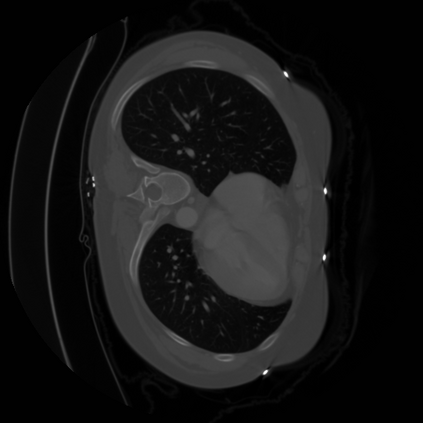

The integration of deep learning systems into healthcare has been hindered by the resource-intensive process of data annotation and the inability of these systems to generalize to different data distributions. Foundation models, which are models pre-trained on large datasets, have emerged as a solution to reduce reliance on annotated data and enhance model generalizability and robustness. DINOv2 is an open-source foundation model pre-trained with self-supervised learning on 142 million curated natural images that exhibits promising capabilities across various vision tasks. Nevertheless, a critical question remains unanswered regarding DINOv2's adaptability to radiological imaging, and whether its features are sufficiently general to benefit radiology image analysis. Therefore, this study comprehensively evaluates DINOv2 for radiology, conducting over 100 experiments across diverse modalities (X-ray, CT, and MRI). To measure the effectiveness and generalizability of DINOv2's feature representations, we analyze the model across medical image analysis tasks including disease classification and organ segmentation on both 2D and 3D images, and under different settings like kNN, few-shot learning, linear-probing, end-to-end fine-tuning, and parameter-efficient fine-tuning. Comparative analyses with established supervised, self-supervised, and weakly-supervised models reveal DINOv2's superior performance and cross-task generalizability. The findings contribute insights to potential avenues for optimizing pre-training strategies for medical imaging and enhancing the broader understanding of DINOv2's role in bridging the gap between natural and radiological image analysis. Our code is available at https://github.com/MohammedSB/DINOv2ForRadiology